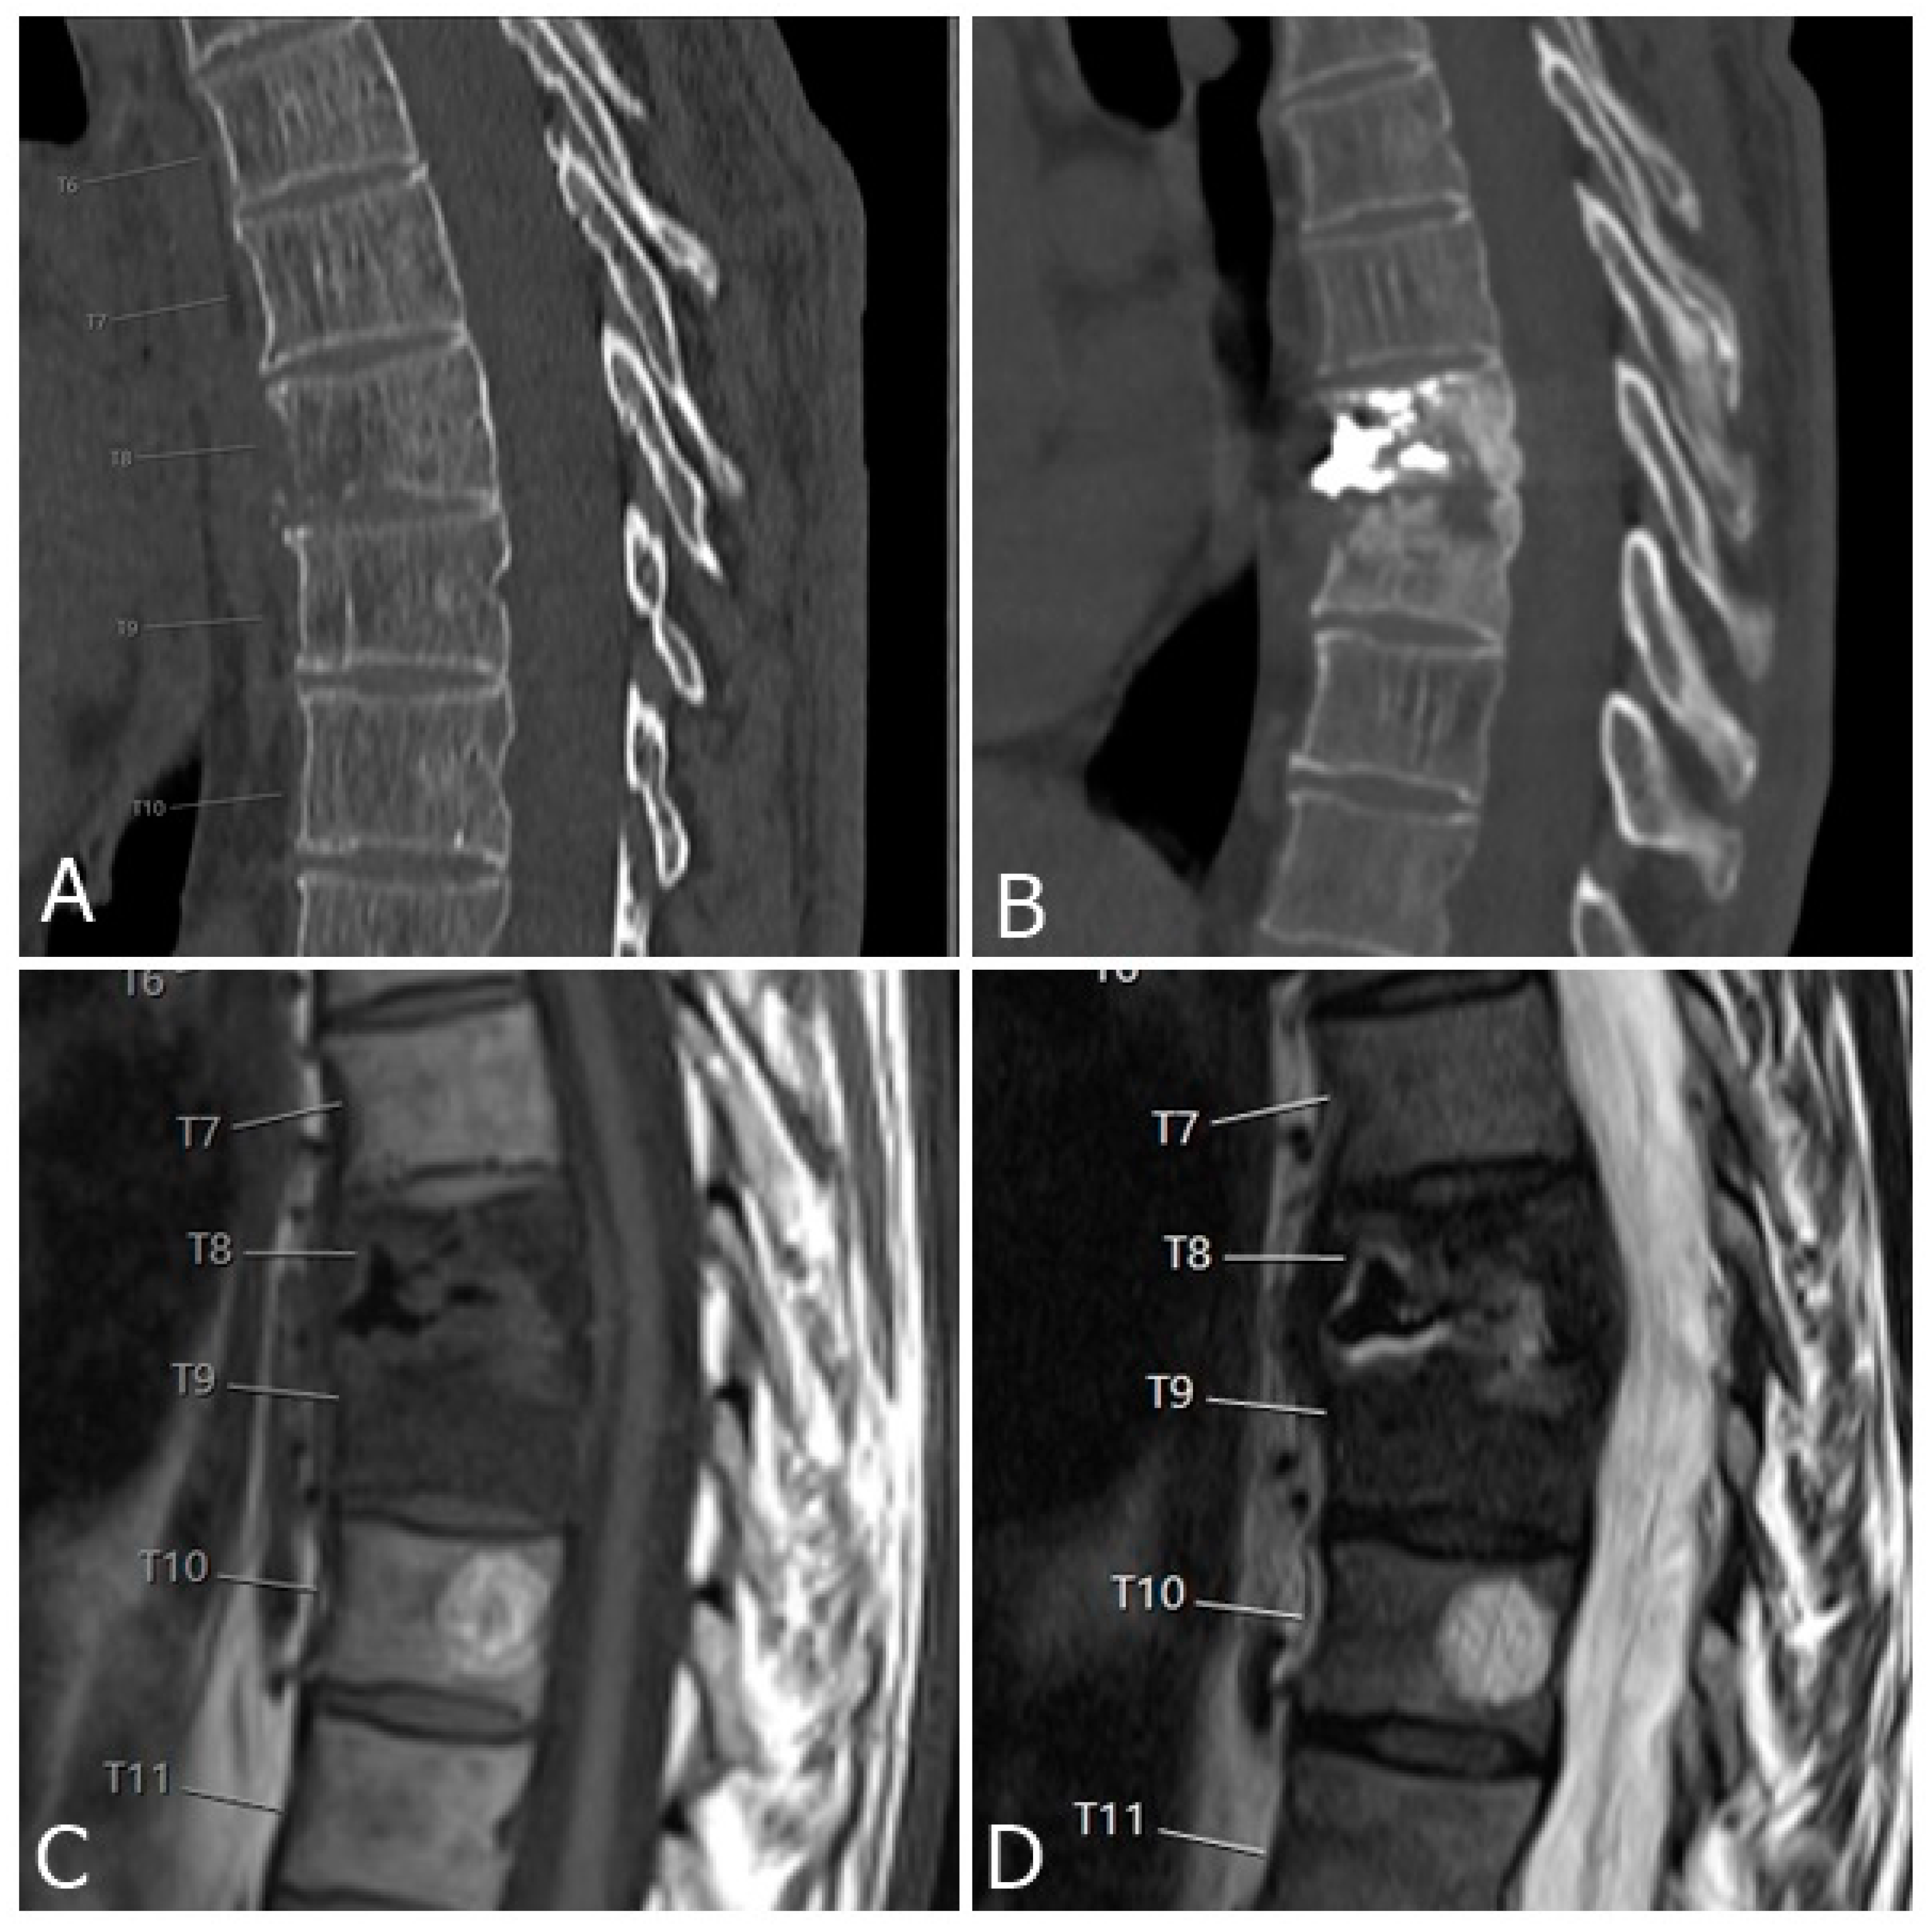

3.1. Epidural and Foraminal Cement Leakage

3.2. New Vertebral Fractures